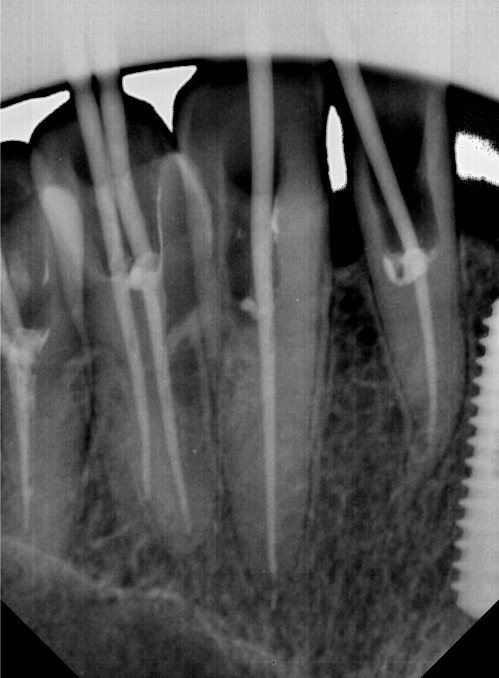

CR/DR 牙齿分割阶段记录

当前进展

- 完成了 CR/DR 牙齿相关分割训练

- 当前结果已经达到阶段预期,但仍有细节问题需要继续处理

相关测试

遇到的问题

- 训练过程中出现过 mask 下移问题

- 部分结果会出现 box 填充异常

- mask 边缘仍然有比较明显的锯齿感

参考

第二版算法问题测试

第三版算法分辨率效果比较

| 编号 | 原图 | 第一版 | 第二版 | 第三版 1216x1600 | 第三版 768x1024 | 第三版 1120x1120 |